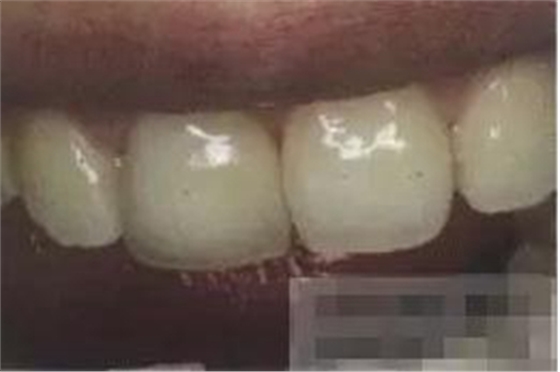

【初步修整】

對(duì)于唇面,首先使用火焰狀車針進(jìn)行修整,一般不使用輪狀車針修整線角

微細(xì)的表面結(jié)構(gòu)最后使用鎢鋼拋光車針成形的。

修整完成

拋光目的:表面光滑 咬合關(guān)系 邊緣適應(yīng) 最少的菌斑附著 易于菌斑去除 美觀性